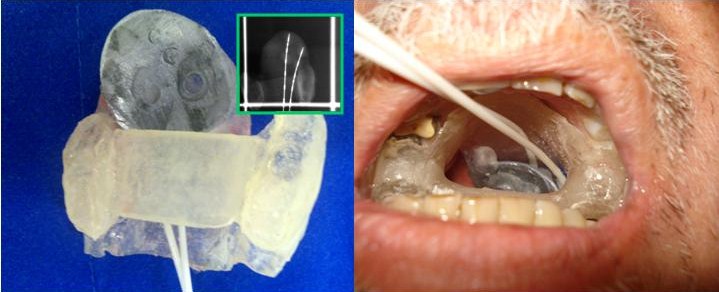

O carcinoma epidermoide de palato mole (CEPM) é uma neoplasia de baixa prevalência que representa a minoria dos tumores que podem acometer a orofaringe. Quando diagnosticados em estádios iniciais, as opções de radioterapia ou cirurgia são aventadas para abordagem terapêutica com taxas de controle locorregional e sobrevida semelhantes. Este estudo tem como objetivo: relatar o caso de um paciente encaminhado ao Departamento de Radioterapia do Centro de Oncologia do Hospital Sírio-Libanês com diagnóstico de CEPM e tratado de forma curativa com radioterapia (teleterapia com técnica de modulação de intensidade de feixe e braquiterapia de altas doses com irídio -192).